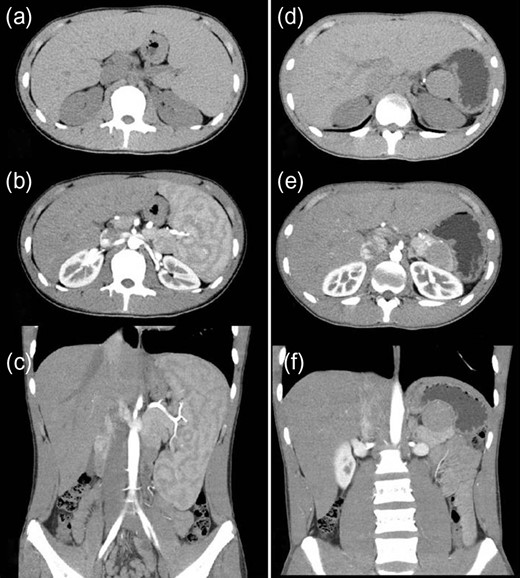

A 16-year-old boy was admitted with a rapidly growing pancreatic mass. He had received a diagnosis of HS based on the following: the need for a blood transfusion to treat anemia after birth, a history of hemolytic anemia, and a family history of HS. He had often undergone medical examinations for anemia and jaundice in junior and senior high school. When he was 15 years old, he visited our hospital because of the rapid onset of jaundice. Radiological examinations, such as computed tomography (CT) (Fig. 1a–c) and magnetic resonance imaging (MRI) (Fig. 2a–c), showed a huge spleen and a 2-cm mass near or in the pancreatic tail. Sonazoid-enhanced ultrasonography showed hypervascularity in the mass, which appeared to be located near the pancreatic tail and raised suspicions about an accessory spleen (Fig. 3a). The patient underwent a successful splenectomy by laparotomy, but the mass found on the preoperative examination could not be found by inspection and intraoperative ultrasonography (Fig. 4a and b). The mass grew rapidly to 4 cm one year after splenectomy, as shown on the radiological examinations (Figs 1d–f, 2d–f and 3b), but a recurrence of HS with anemia or jaundice did not develop. However, he underwent successful laparoscopic surgery to aid in the differential diagnosis. After the adhesions of the omentum to the abdominal wall were detached, the laparoscopic ultrasonogram revealed the mass in the pancreatic tail. He underwent laparoscopic distal pancreatectomy (Fig. 4c and d), and he had no clinical symptoms or signs of local infection or sepsis. A CT on the ninth postoperative day showed a small peripancreatic collection (Grade B: the clinical grading of postoperative pancreatic fistula). He was discharged on the 11th postoperative day. The resected specimen revealed the intrapancreatic mass that was covered with pancreatic tissues, and the intrapancreatic mass was an accessory spleen (Fig. 4e).

Computed tomography (CT) (before and after splenectomy). (a–c) Before splenectomy: Plain and enhanced CT shows a huge spleen and a 2-cm mass near or in the pancreatic tail. (d–f) After splenectomy: Plain and enhanced CT shows the mass in the pancreatic tail grows rapidly to 4 cm.